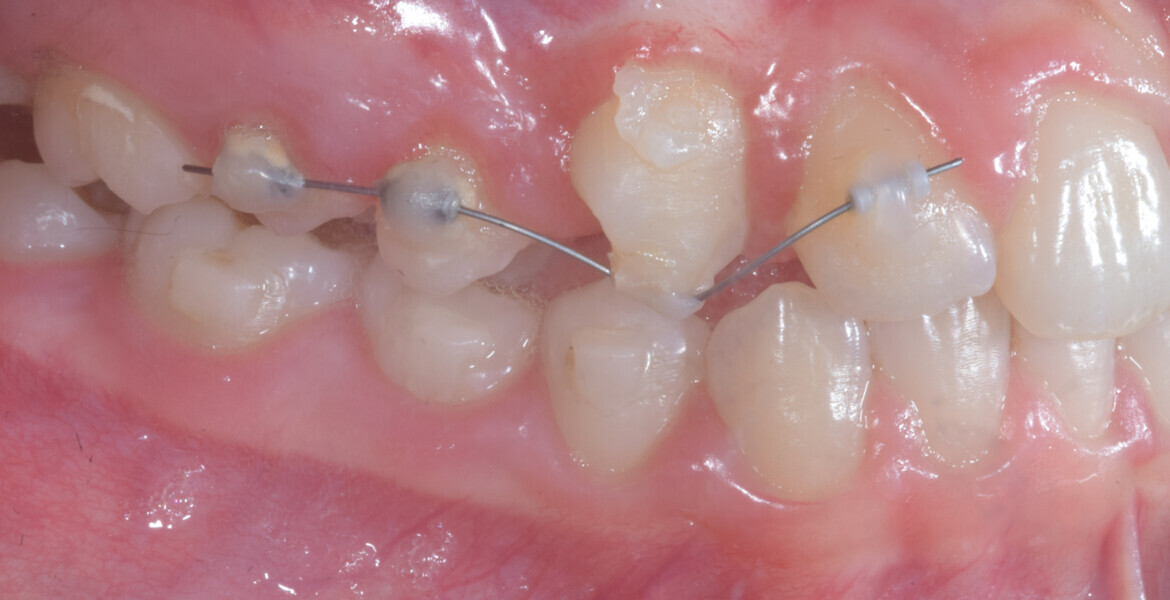

At the same time, the impacted canine was exposed by laser, a button was bonded on to it and the cantilever was connected to the button using an elastomeric thread. The final aligner was used for space maintenance while the cantilever was reactivated until the canine had erupted (Figs. 25–27). After complete eruption, further MTAs were bonded on the canine and on the lateral incisor, and a 0.014 in. NiTi archwire was used to finalise the eruption (Figs. 28–30). Only at the end of the forced eruption phase did the further aligner stage take place, aimed at achieving an ideal Class I relationship on the right by maxillary right mesialisation using Class III elastics and 27 maxillary aligners and 13 mandibular aligners (Figs. 31–33).